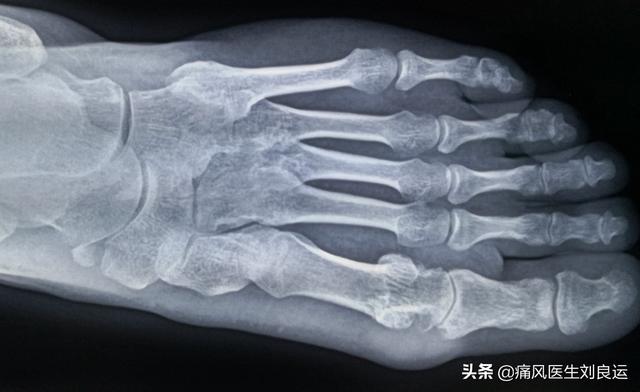

典型的な急性痛風性関節炎は通常単関節に発症し、初発の70%は第1中足趾節関節に起こり、次いで中足趾節関節、中足趾節関節、足関節、指関節、手関節と続き、再発する場合は膝関節や肘関節にも起こる。

急性痛風性関節炎における関節痛は、血液中の分解しきれない尿酸が関節や軟骨、滑膜などに析出して結晶塩を形成することが主な原因です。尿酸塩結晶がある程度集まると、尿酸の急激な急上昇や急降下によって結晶が剥がれ落ちると、血液中の免疫細胞で免疫反応が起こり、炎症物質が放出されて炎症が起こります。

私たちが知っているように、痛風の発症は、長い時間のための体の尿酸値に基づいている標準を超え、血液中の尿酸が完全に溶解することはできません、尿酸塩結晶の形成は、関節や体の他の部分に堆積した。尿酸塩結晶の局所濃度のこれらの部分が高すぎる場合、体の免疫システム "アラート "を引き起こし、これらの "歓迎されない "をクリア "悪いこと"、ローカルの激しい痛みをもたらす、体の免疫系がこれらの「歓迎されない」「悪いもの」を除去するために「警告」されると、局所的な激しい痛み、発赤、腫れ、その他の炎症反応、痛風発作の症状につながる。体内の尿酸濃度が痛風発作の最も重要な原因であると言える。痛風発作の再発は、尿酸濃度の頻繁かつ急激な変化によって引き起こされる。

痛風は、血中の尿酸値が飽和値を超えて上昇し、関節などの組織に尿酸ナトリウム結晶が析出・沈着することによって起こる結晶性関節症である。痛風が治りにくいのは、一度できた尿酸結晶が完全に溶解・排出されにくく、誘因因子の作用を受けて再び痛風発作を起こすからである。